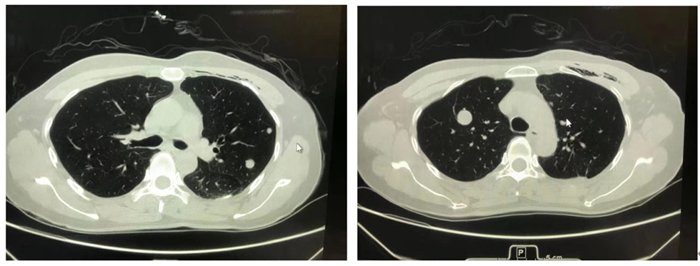

图1 图2

图1、2胸部CT图片分别显示左、右侧肺部(黑色)类圆形灰白结节,好似“夜空中的一轮圆月”

王志敢主任医师介绍,肺部良性转移性平滑肌瘤(PBML)主要发生于育龄期有子宫肌瘤或子宫切除病史的女性。患者无特异性临床表现, CT表现为双侧肺部(黑色背景)多发大小不一类圆形结节(白色),具有一定特征,可以形象地称为“夜空中的一轮圆月”。偶尔可为肺部单发结节。罕见情况下可发生于心血管、骨骼肌、淋巴结等部位。该肿瘤因生长缓慢,不会严重影响肺功能,可带瘤生存数十年,因此极易漏诊。自首次报道该肿瘤至2020年6月,有人在WJCC(World Journalof Clinical Cases)杂志上统计全球仅有100例。近10年来,香港马会app